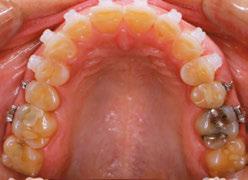

Figures 6 through 9 demonstrate a patient successfully treated with NiTime Aligners following the patient’s rejection of other systems. Figures 6 and 8 display pre- and posttreatment photos of a patient that presented with a Class II malocclusion and normal OB/OJ. This patient has teeth Nos. 7 and 10 missing congenitally. Note that the patient was treated as a child and has a canine substitution due to the missing lateral incisors. Recession was noted on tooth Nos. 2,3, 4, 5, 9, 11, 13, 14, 22, 24, 26, and 27. The patient tried labial and lingual brackets unsuccessfully, as well as a leading clear aligner to correct her malocclusion as an adult. In all three treatments, the patient could not tolerate the mechanics due to increased discomfort and was unable to complete therapy.

It is important to note that there was no refinement required for this case, and the patient finished in 26 weeks with 26 trays. Although the patient presented with significant recession, it did not worsen with treatment. As demonstrated in Figure 9, teeth aligned as planned by the OrthoFX treatment plan shown in Figure 7. Overlays of the actual results with the original treatment plan indicate a high level of predictive accuracy. Not only was a satisfactory result produced from the patient wearing the aligners, but the accuracy is quite high for the NiTime material despite the patient wearing it significantly less than the traditional 22 hours per day.

Figure 7: Predicted results from the OrthoFX treatment plan